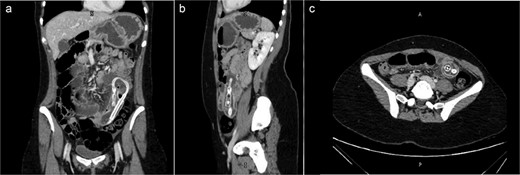

After she arrived in the emergency room, plan X-ray abdomen showed dilated jejunal loops and an ultrasound (US) of her abdomen was carried out, and it was discovered that the gastric balloon in the left upper quadrant of the stomach lumen had drastically shrunk, indicating that it may have ruptured (Fig. 1). Nevertheless, the balloon was not visible during the upper endoscopy that she had later.

(a) Plan X-ray abdomen showing dilated jejunal loops. (b) Abdominal US showing small bowel containing IGB.